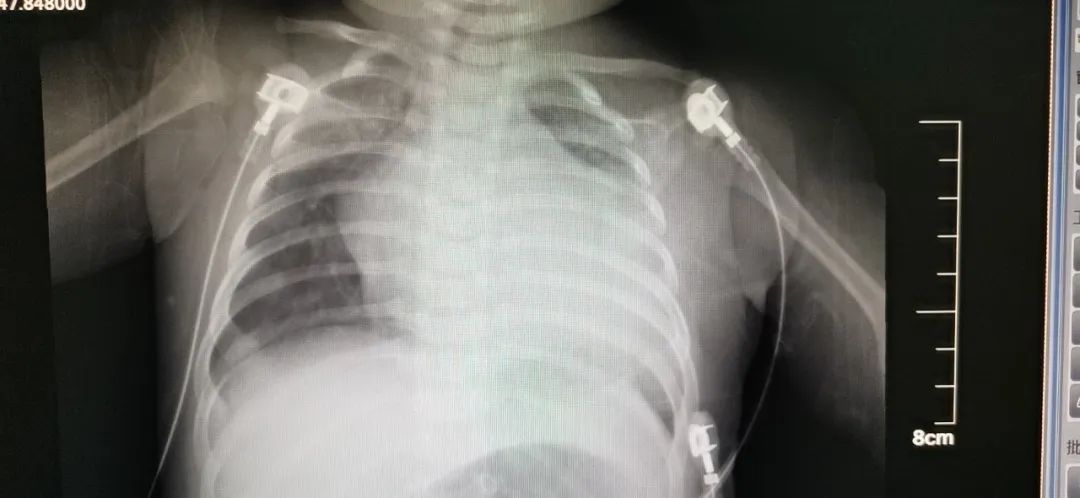

2月中旬,小新突然出现喘气快,不爱吃奶,脸色发青的症状。这可急坏了小新父母,虽然疫情严峻,还是赶紧带着孩子去了当地某三甲医院,当时医生检查发现小新的心脏相比同龄孩子“大”的多,考虑孩子患有先心病、重症肺炎。但经过当地医护人员几天的抗感染、强心利尿等对症处理,小新的病情却没有明显好转。当地医院无法,建议其前往青岛妇儿医院心脏中心就诊。

完善相关检查后,心脏中心医护人员发现:初步床旁急诊超声检查提示小新的左冠状动脉起源异常,射血分数仅30%(正常50-70%)。这是一种非常严重的复杂先心病,一般早期不易发现,出现症状后心脏扩大非常明显,由于生后一两个月肺动脉压力的下降,异常起源于肺动脉的左冠状动脉出现逆灌,导致左心供血不足,缺血缺氧导致扩张,严重的还出现二尖瓣腱索断裂,瓣叶挛缩,心功能急剧恶化,很多被误诊为扩张性心肌病或心内膜弹力增生症,如果不及时手术治疗,心衰继续加重,可能猝死。

医务人员进一步为患儿进行CTA以及心导管造影,明确小新就是患有左冠状动脉起源异常。这是一种发现即需要尽早手术的亚急诊手术,只有通过手术才能挽救生命。